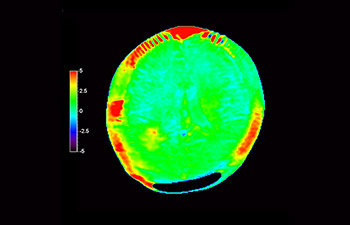

Neurologische Leiden stellen eine schwere Belastung dar. Philips hat es sich zum Ziel gesetzt, hochwertigste Neuro-Bildgebung zu ermöglichen – für eindeutige Diagnosen und eine schnelle Therapie. Wenngleich die MRT heutzutage den Goldstandard in der neuroradiologischen onkologischen Bildgebung darstellt, kann die Genauigkeit beim Tumor-Grading und den Nachsorgeuntersuchungen noch weiter verbessert werden. 3D APT (Amide Proton Transfer) ist eine einzigartige, kontrastmittelfreie Methode zur MR-Tomographie des Gehirns, die den Bedarf nach einer sichereren Diagnose in der Neuroonkologie erfüllt. 3D APT nutzt das Vorhandensein von endogenen zellulären Proteinen zur Erzeugung eines MR-Signals, das direkt mit der Zellproliferation, einem Marker für Tumoraktivität, korreliert. 3D APT kann geschulte medizinische Fachkräfte dabei unterstützen, gering differenzierte von hochdifferenzierten Gliomen und Tumorverhalten von Behandlungseffekt zu unterscheiden1.

mit 3D APT